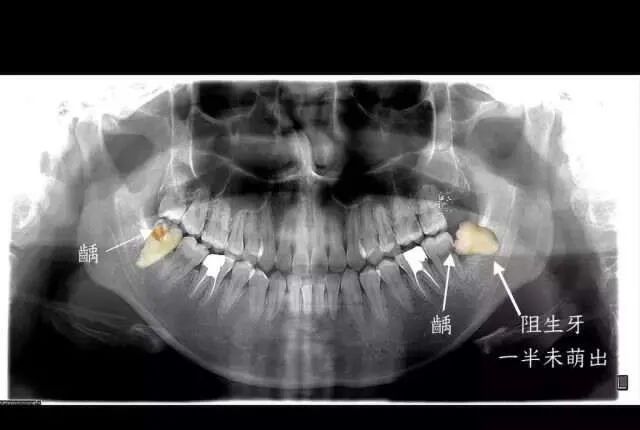

拔牙的原因很多,但是最簡單的一種判斷方式就是,這個(ge) 智齒是否長得足夠正。言下之意就是,盡管暫時還沒有引起疼痛,那些長歪的智齒也是越早拔除越好。

原因就在於(yu) 長歪的智齒非常不容易清潔,食物常常會(hui) 殘留,有的就會(hui) 導致智齒及周圍組織疼痛,更嚴(yan) 重的是,它還會(hui) 導致智齒前方的磨牙出現蛀牙,進一步則出現牙痛,最嚴(yan) 重的、也非常常見的狀況是,智齒要拔掉先不說,連同智齒前方的第二磨牙都出現不可挽救的齲壞,隻能一起拔掉。

智齒前方的牙齒已經出現了蛀洞,即齲病。圖源:作者